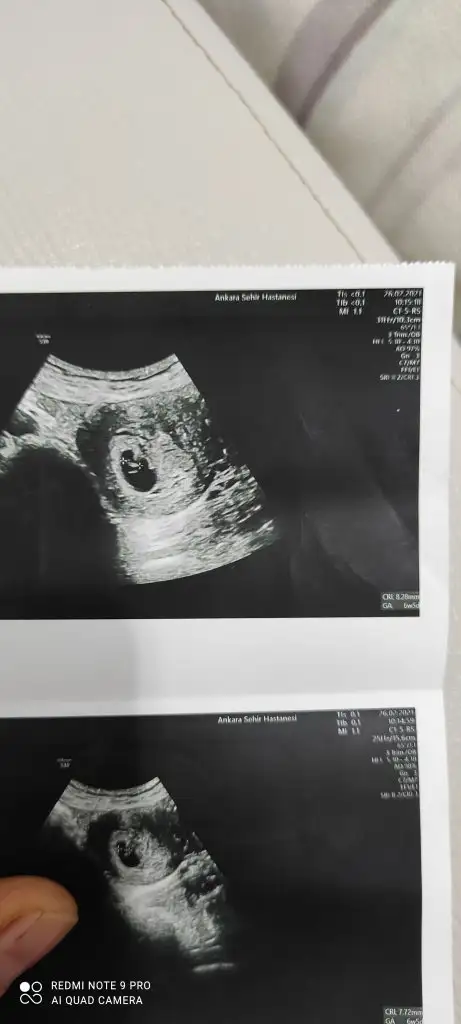

8 +2 Banada bir tahmin yürütürmüsünz:)

Eklentiler

• IMG_20210419_101243.webp

IMG_20210419_101243.webp

36,4 KB · Görüntüleme: 84